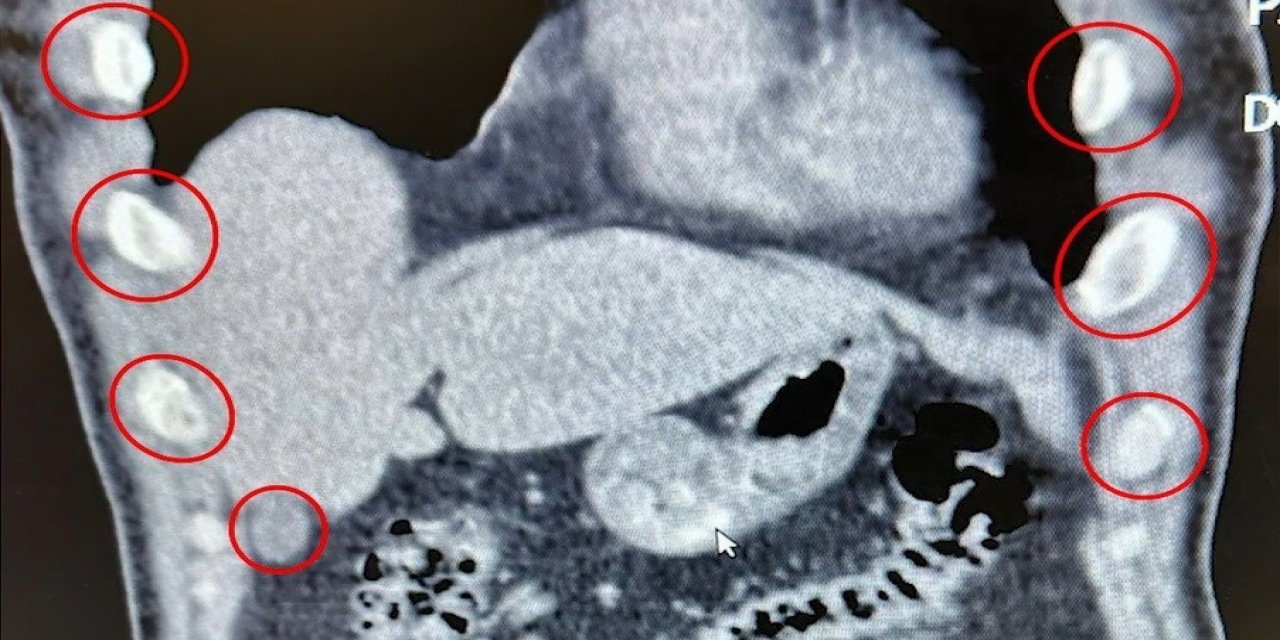

Mideye saklanan 136 uyuşturucu kapsülü ele geçirildi